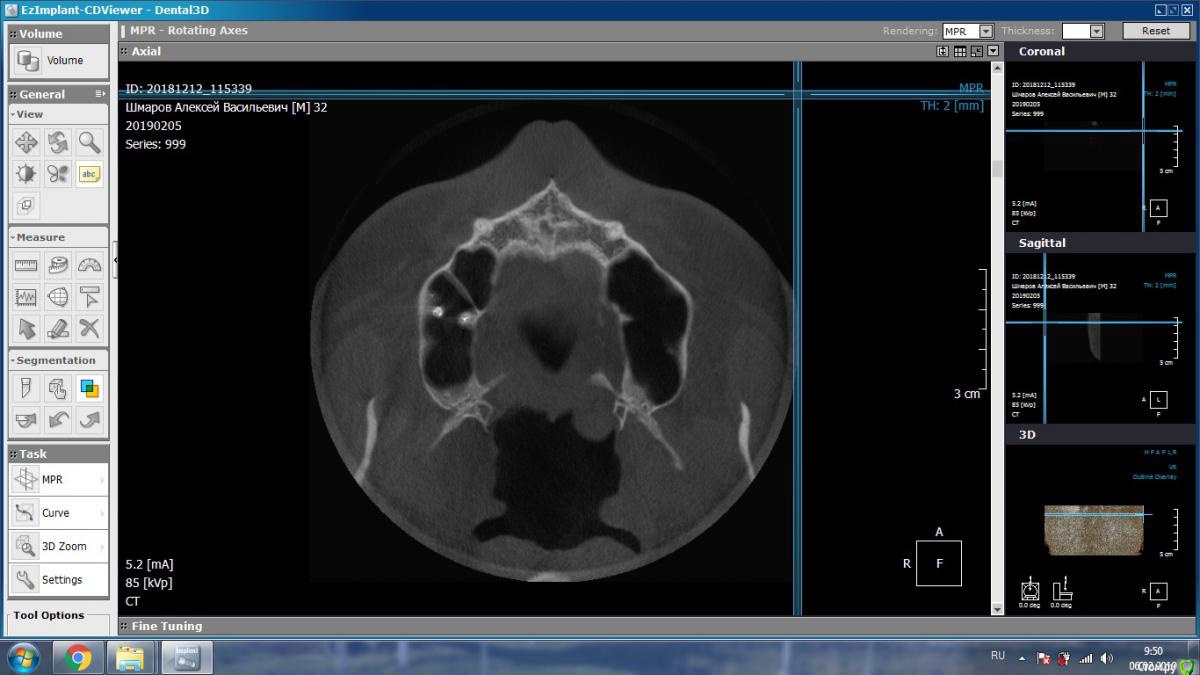

DmitrySH Опубликовано 5 февраля, 2019 Поделиться Опубликовано 5 февраля, 2019 Такие подойдут? В Аксиальной проекции покажите еще несколько срезов Ссылка на комментарий

aleks.k Опубликовано 6 февраля, 2019 Автор Поделиться Опубликовано 6 февраля, 2019 Срезы Ссылка на комментарий

aleks.k Опубликовано 6 февраля, 2019 Автор Поделиться Опубликовано 6 февраля, 2019 Еще один срез, может быть более удачный чем первые в этой проекции Ссылка на комментарий

DmitrySH Опубликовано 6 февраля, 2019 Поделиться Опубликовано 6 февраля, 2019 Срезы Очень хорошо. Теперь как первые три, но увеличить 16 зуб. Остальные нам мало интересны, пазуха тоже Ссылка на комментарий